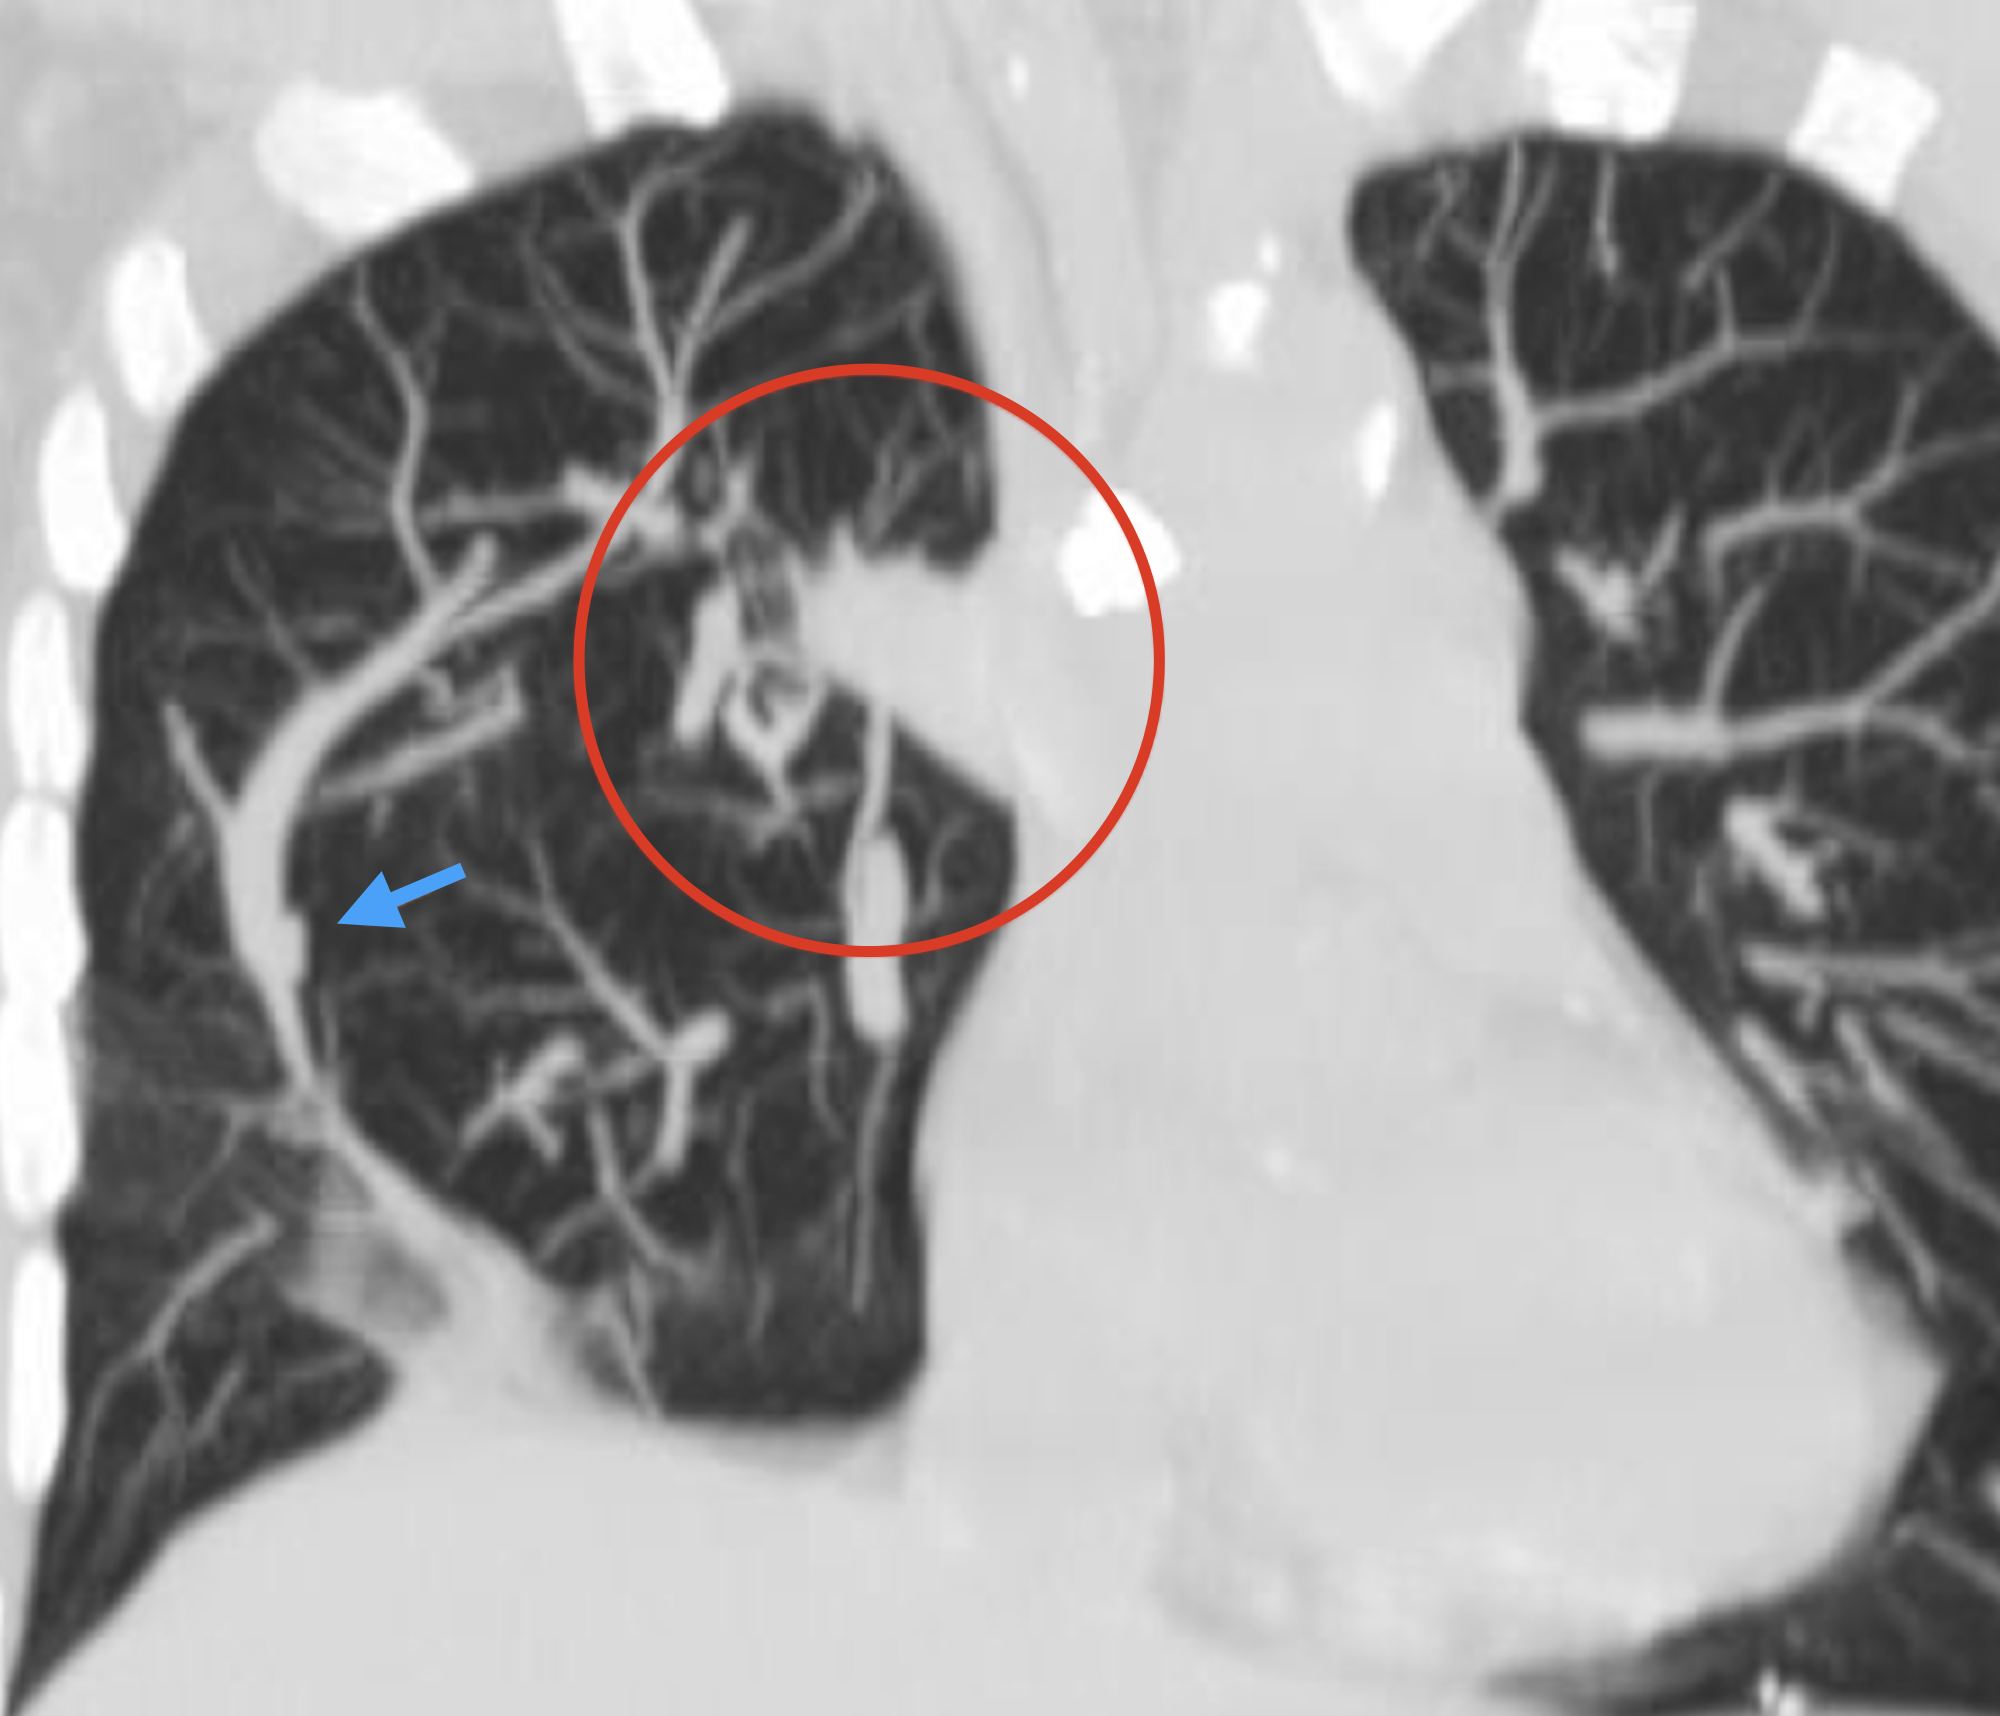

Image | Radiopaedia.org